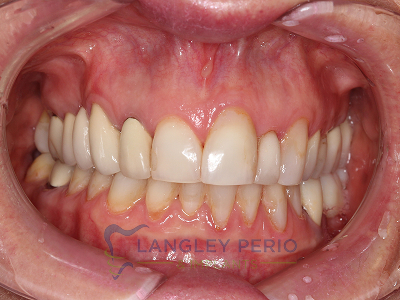

Case 2

Connective tissue grafting was done to cover exposed root surfaces to help to prevent root cavities from developing and reduce temperature sensitivity.